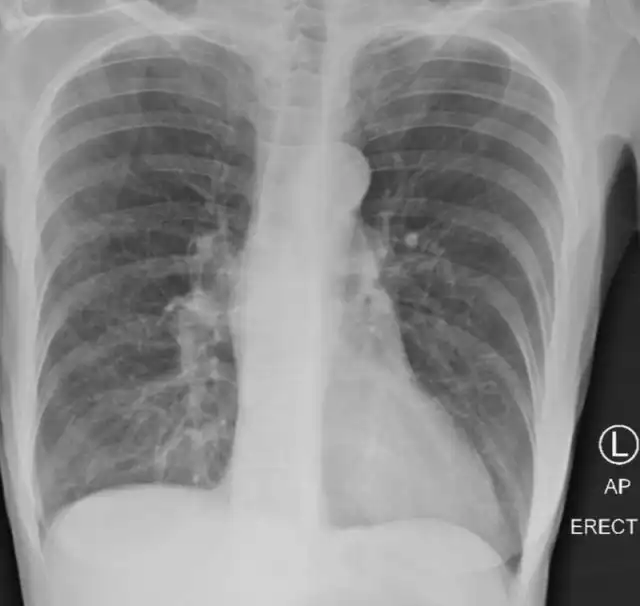

Это лёгкие курильщика.